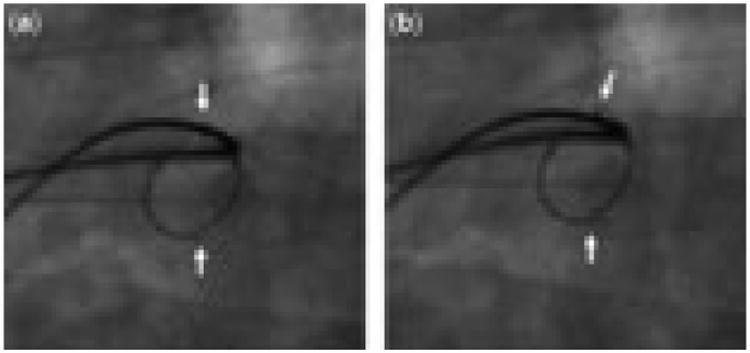

Figure 4.

This central right pulmonary arterial stent in a patient with common arterial trunk and interruption of the aortic arch is fractured along superior and inferior axial planes, but is only mildly distorted in its geometry. Over the course of a cardiac cycle, two points of which are demonstrated in (a) and (b), the torsion and compression of the vessel can be appreciated by the movement of the fractured edges of the stent (arrows) relative to one another.

The manifestations of fracture may vary considerably. The effect of fracture and compression on luminal size and haemodynamic obstruction is a function both of the relief of stenosis from angioplasty and stenting in the first place, and the cross-sectional area of the lumen. When exposed to very high or complex multiaxial compressive forces, a fractured stent may collapse almost completely, or fracture along multiple planes, resulting in a vascular cross-section that takes a lenticular shape (Fig. 1). Severe eccentricity was observed in one-fifth of fractured stents, and in three-tenths of cases there was severe obstruction of the stented pulmonary arterial segment (Fig. 3). On the other hand, most of the fractures identified were associated with modest collapse and mild obstruction. In some of these cases, the compressive forces acting on the stent may be such that very little deformation of the cross-sectional geometry occurs once the point of plastic deformation has been reached, and in others, the fractured edges of the stent overlap, with the contour of the separate segments remaining more or less intact, resulting in a relatively circular cross-sectional area, only with a smaller diameter (Figs. 2 and 4).

By definition, the structural integrity of a stent is compromised once the yield point is reached, with the transition from elastic to plastic deformation. Clinically, we can consider whether the compromised structural integrity leads to impaired therapeutic efficacy, that is, whether the fractured stent is able to serve its purpose of stenting the vessel open. Of course, it is difficult to assess the relative importance of the underlying lesion and the fracture itself as contributors to recurrent obstruction, but effectiveness of the fractured stent was compromised to some extent in most cases, and severely in one-third (Figs. 1 and 3). Both redilation and restenting were attempted to relieve recurrent obstruction. In cases of mild obstruction, redilation without stenting often provided relief. In all cases of restenting within the fractured stent, this manoeuvre was acutely successful, although among the 8 vessels studied after restenting, fracture recurred in 3.